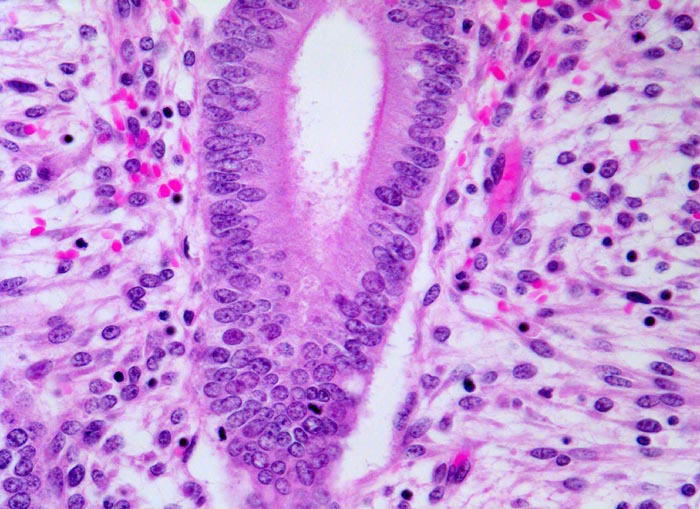

PathoPic ID 4748 - Mittlere Proliferationsphase des Endometriums

Mittlere Proliferationsphase des Endometriums

Normalbefund

Endometrium

Genitalorgane, weiblich

Epithel hochzylindrisch, Kerne länglich chromatinreich mit Mitosen. Stroma aufgelockert.

Uterus myomatosus

Histologie

200